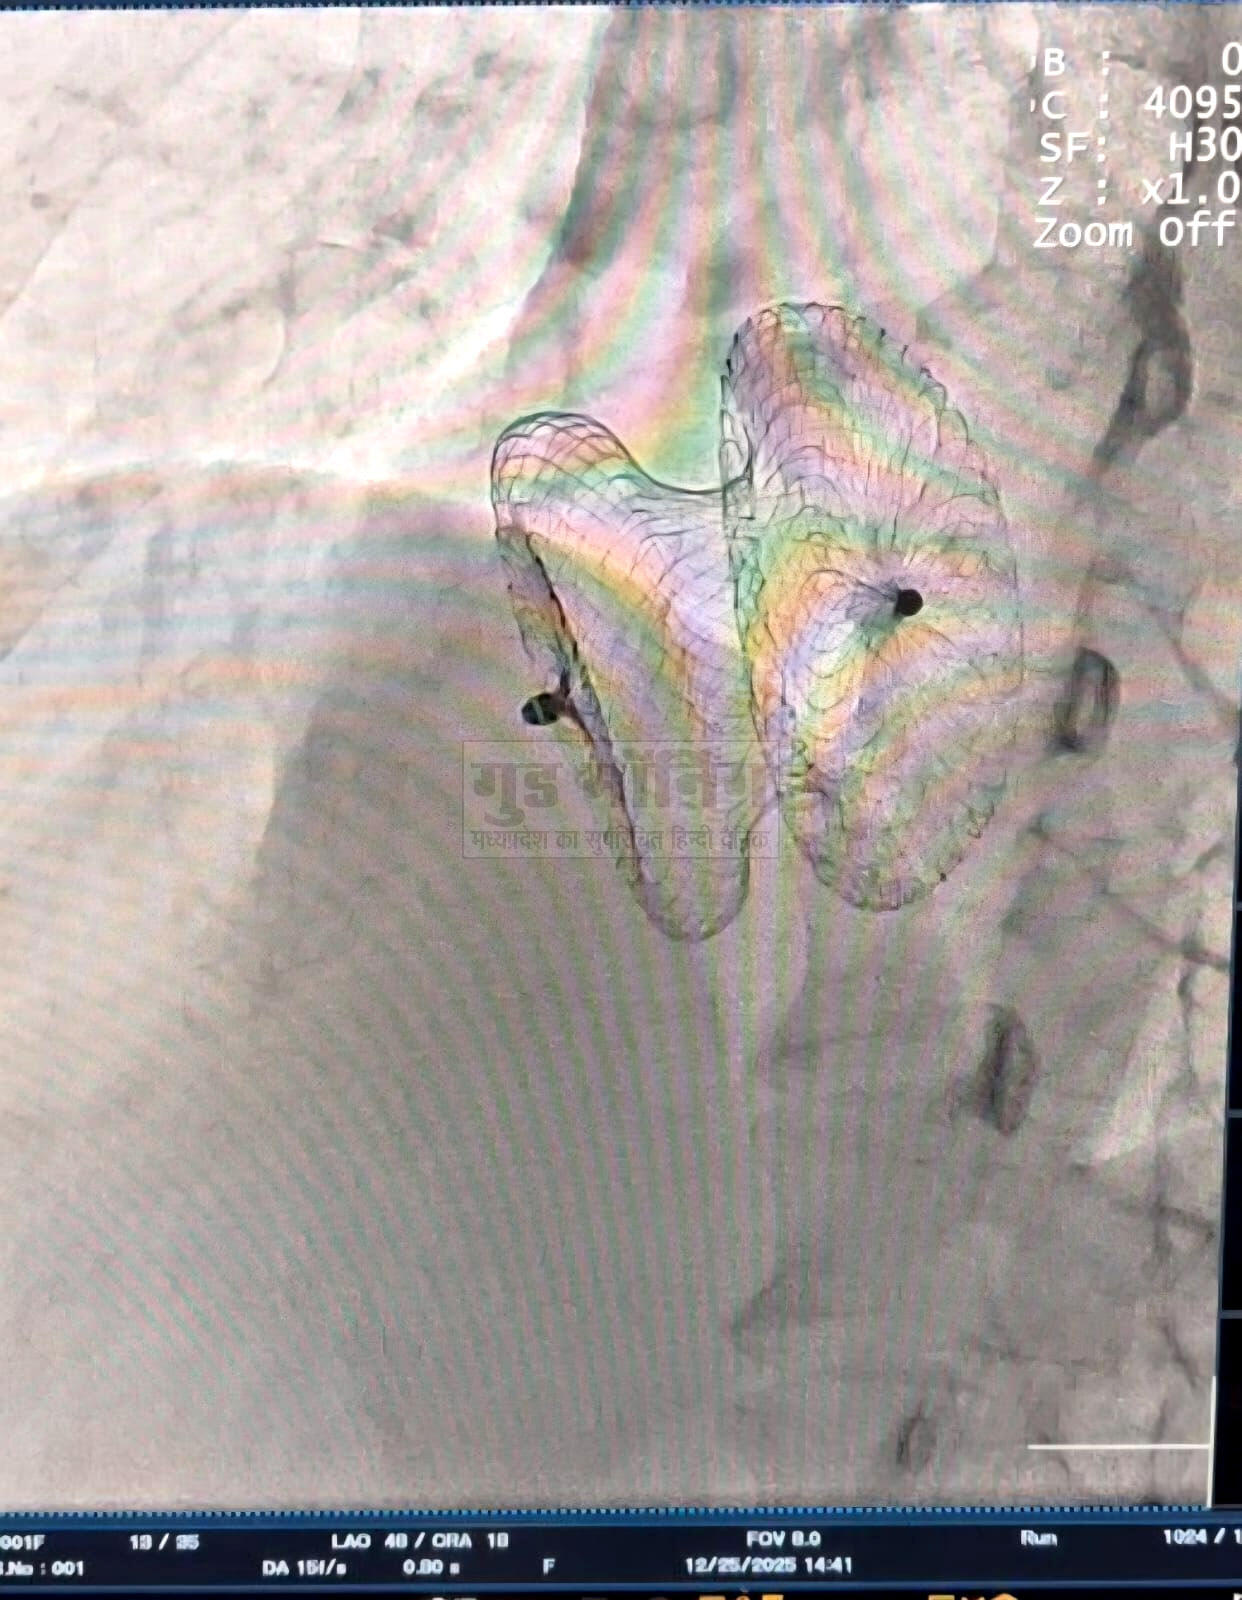

रीवा। सुपर स्पेशलिटी हॉस्पिटल रीवा के कार्डियोलॉजी विभाग ने एक नया कीर्तिमान स्थापित किया है। डॉ. एसके त्रिपाठी एवं डॉ. सुरेंद्र तिवारी की अगुवाई में टीम ने दो मरीजों के दिल में बड़े जन्मजात छेद (एट्रियल सेप्टल डिफेक्ट -एएसडी) को बिना ओपन हार्ट सर्जरी के, मात्र एक छोटी सी डिवाइस के माध्यम से सफलतापूर्वक बंद कर दिया।

यह आधुनिक प्रक्रिया पहले केवल बड़े चीरे और ओपन हार्ट सर्जरी से ही संभव थी, लेकिन अब कैथेटराइजेशन तकनीक से बिना किसी टांके या बड़े ऑपरेशन के यह इलाज हो रहा है। सबसे महत्वपूर्ण बात यह है कि विंध्य क्षेत्र में पहली बार एक ही समय में दो एएसडी डिवाइस क्लोजर प्रक्रियाएं सफलतापूर्वक संपन्न हुई हैं - यह क्षेत्रीय चिकित्सा इतिहास में एक मील का पत्थर है।